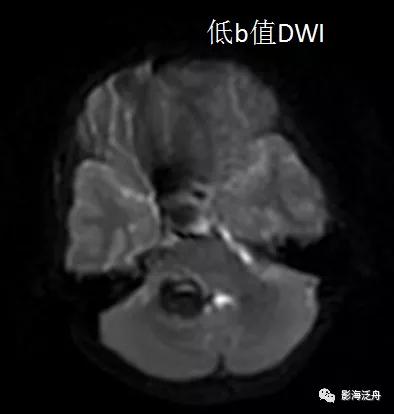

上图可见右侧桥臂一类圆形异常信号,T1WI呈中央稍低信号,边缘环形高信号,T2WI以低信号为主,局部可见液液分层(红箭),高、低b值DWI显示病变区域信号丢失。通过上述信号改变,不难看出是一个急性期血肿(血肿分期详见 MR上脑出血信号的演变机制)。

诊断虽然明确了,但故事到这里还没结束,回过头去看患者第一次检查的低b值DWI序列,可以发现这些病灶其实早就存在。但为什么第一次检查的时候没有及时发现呢?想必这大概率是因为大家对低b值DWI序列认识不足造成的,尤其是低年资诊断医生和神经科临床医生往往会自动忽略掉低b值DWI序列,再或者就是把低b值DWI误认为是高b值DWI序列。

在低b值DWI序列可以看到左侧大脑半球多发磁敏感伪影(红箭)。

从理论上讲,无论高b值DWI还是低b值DWI序列都应该对磁敏感伪影很敏感,但实际情况是不是这样呢?看下图↓↓

上图可以发现,在低b值DWI序列上左侧额顶叶交界区的病灶显示清晰(红箭),但在高b值DWI序列上,除病灶外,多个脑沟也表现出磁敏感伪影(绿箭)。因此,当病灶足够小或者数量比较少的时候很难区分到底是伪影还是病灶,而低b值DWI序列可以较好地解决这一问题。